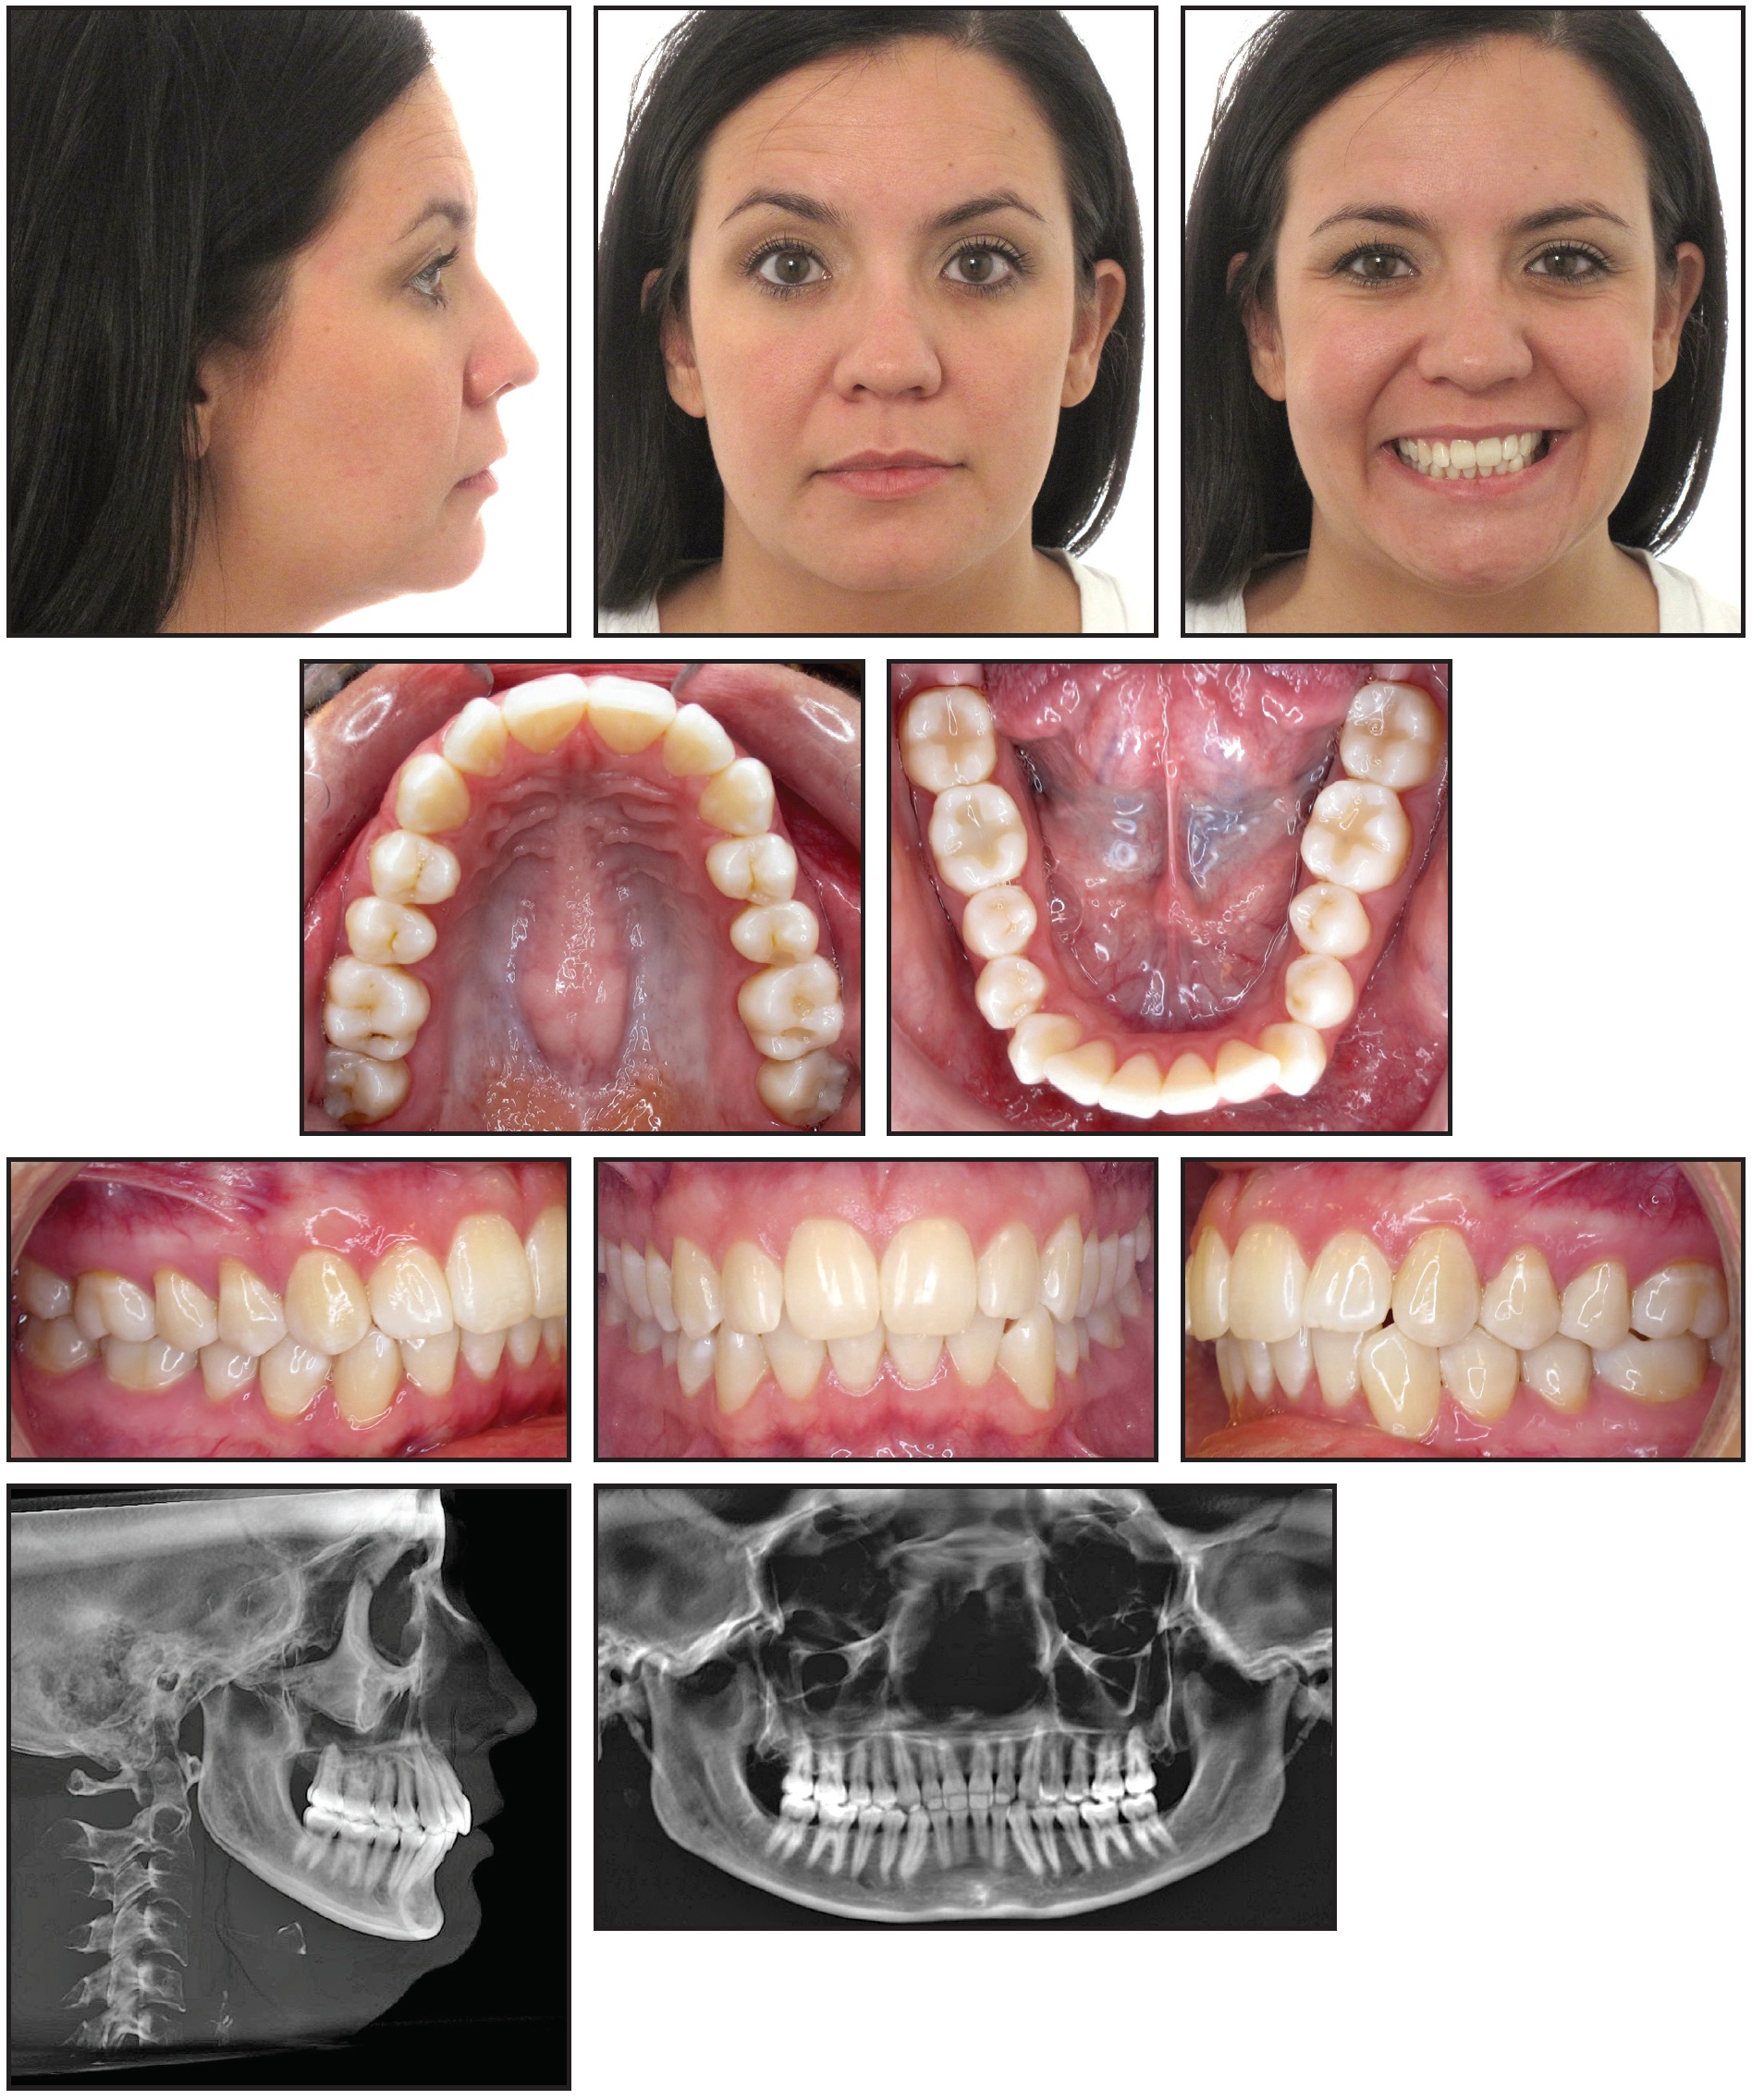

A 31-year-old female presented with the chief complaints of TMD symptoms and a changing bite (Fig. 1A). Her dental history included treatment for trauma-induced TMD at age 8 (with an intraoral neuromuscular device) and again at age 15. The patient stated that her right condyle was a source of pain due to a physical blow to the right side of her face in 1992. She had begun having migraines with photopia and nausea shortly after the incident. The migraines varied in intensity and frequency, with a peak occurrence of three times per day and an intensity as high as 10 out of 10 on the pain scale. The migraines eventually became milder (1 out of 10), and the patient identified caffeine as a trigger. Her physician had prescribed beta blockers, which were unsuccessful, and Topamax,* which produced negative side effects.

Clinical examination found a slightly convex profile with a fuller right side of the face and asymmetrical commissures (lower on the right). The lower facial third was long, and a dental cant was evident; the chin was positioned slightly to the left of the midsagittal plane. The patient had a Class I occlusion with 2-3mm of crowding in the maxillary arch, 4-5mm of crowding in the mandibular arch, and a canted occlusal plane. The overbite and overjet were normal. A Bolton discrepancy was attributable to excessive tooth size in the mandibular arch. The TMJ complex showed a maximum opening of 45mm with a 10mm range of protrusive, left lateral, and right lateral movements. The right and left external pterygoid muscles were tender on palpation; the left condyle clicked on lateral movements, while the right clicked on opening (Fig. 1B).

Fig. 1 31-year-old female patient with previous TMD treatment, Class I occlusion, Class II skeletal relationship, canted occlusal plane, lower Bolton discrepancy, and 45mm maximum TMJ opening before treatment (continued in next image).

Fig. 1 (cont.) 31-year-old female patient with previous TMD treatment, Class I occlusion, Class II skeletal relationship, canted occlusal plane, lower Bolton discrepancy, and 45mm maximum TMJ opening before treatment.

Cephalometric analysis indicated a Class II skeletal relationship, due to a slightly retrognathic mandible, and a steep mandibular plane. The panoramic radiograph showed parallel roots, previously extracted third molars, and a short ramus on the left side. The right TMJ evidenced remodeling with a posterosuperior loss of volume, thin joint space, posteriorly positioned condyle, and flattened eminence. The left TMJ exhibited inactive degenerative joint disease with a posterosuperior loss of volume, thin joint space, posteriorly positioned and small condyle, flattened eminence, and anterior osteophyte.